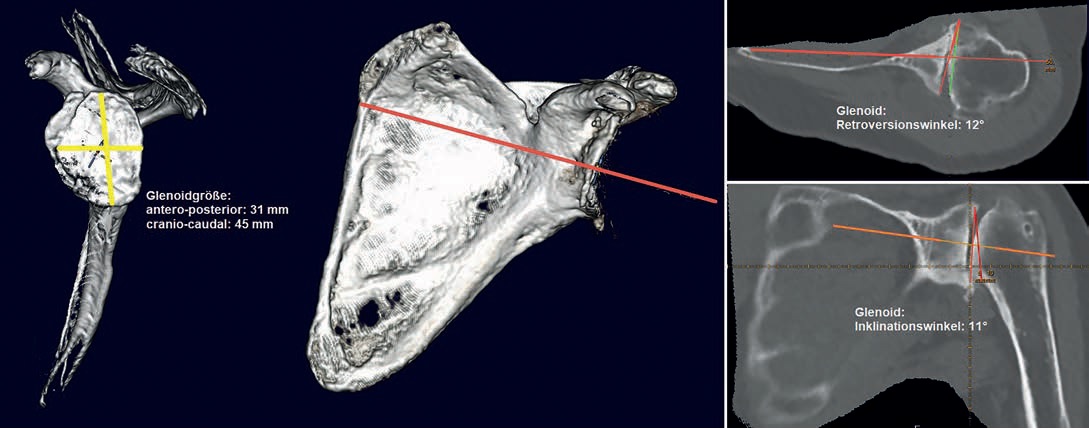

schneller. Ich brauche bspw. zwischen 5 und 10 Minuten für eine normale Schulterplanung. Für eine 3D-Planung

mit einer 3D-Gelenkrekonstruktion inklusive animierter 3D-ROM-Analyse und Betrachtung des Gelenkes aus verschiedenen

Blickwinkeln, so wie es aktuell mit der Software mediCAD® Shoulder 3D ermöglicht wird, brauche ich derzeit noch

Ich versuche bei jeder anstehenden OP mindestens eine digitale 2D-Planung, idealer Weise sogar eine 3D-Planung zu

machen. 3D-Planungen basieren aber auf CT-Bildern, und leider habe ich nicht immer ein geeignetes CT in der entsprechenden

Dünnschicht-Auflösung und Abmessung (ganzes Schulterblatt und Epicondylen ) zur Verfügung, denn viele Patienten

haben nur ein MRT dabei, bei dem meist nicht die eigentlich erforderlichen Endpunkte der betroffenen Knochen

abbgebildet sind und gehen davon aus, dass dies ausreichend sei. Eine digitale 2D-Planung ist aber auch anhand eines

MRT in Annäherung möglich, allerdings mit deutlich eingeschränkter Aussage gegenüber der 3D Planung mit reproduzierbaren

Referenzebenen in den Schulterblattebenen und Humerusachsen.

Deswegen bin ich gerade dabei mit unseren ortsansässigen Radiologen ein mediCAD® CT-Protokoll zu erarbeiten und

dabei die Vorteile der 3D-Planung mit Bestimmen auch der Humerus-Retrotorsion durch Erfassen der Epicondylenachse